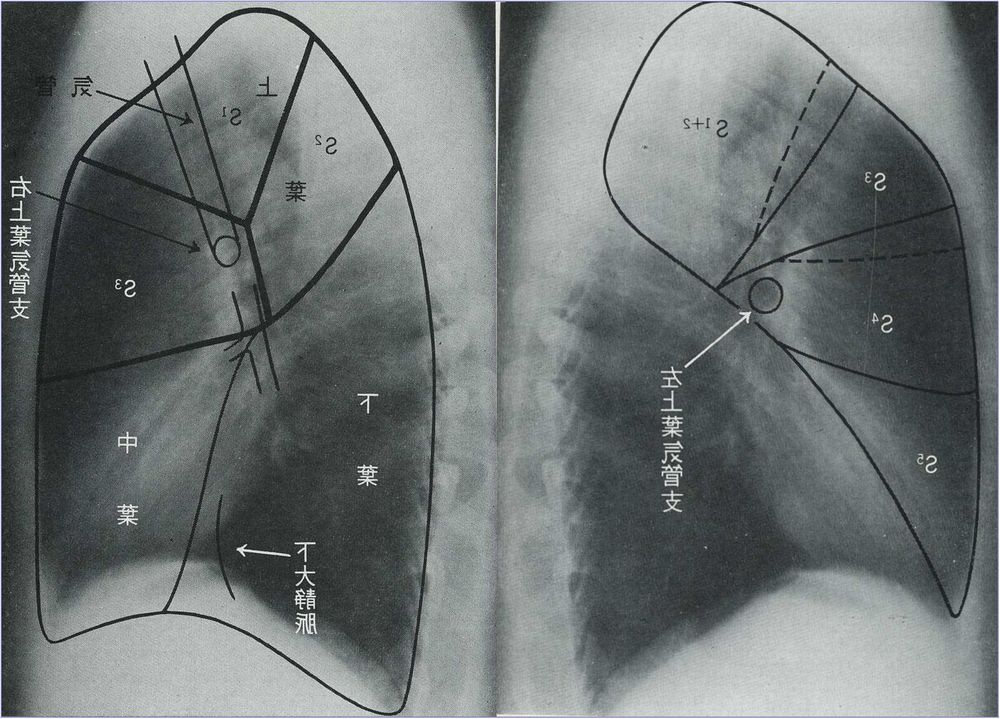

胸腺の腫大により気管が左右に変位することがあります。乳児では胸腺が正常でも腫大しているため、時にこの変化をみとめる。 [実際例] 気管が右に変位、同時に縦隔陰影の拡大があり肺野には気管支肺炎の所見をみとる。気管の変位の部位・変位の仕方で原因の推測が可能になる。 肺の分画 さらに細部をみると気管支の走行によって右肺は10に左肺は8つに分かれ、それぞれの区分に番号が付けられています(下の模式図ならびに実際に近いイラスト参考)。

正面(イラスト)

内側展開図(下図) 背面(下図)(背中側から見ている) 体表からみた肺区域 レントゲン写真に投影する肺区域 レントゲン側面像(展開像:魚の開きのイメージ) 肺・気管支のイメージ 気管支の分枝 肺の血管走行 肺門部のリンパ節 A-P window 大動脈と肺動脈の交差する部位、リンパ節腫大の目印になります。 肺野の区分 肺野を便宜的に3等分して肺野での位置を表示するために使用します。 縦隔陰影・心陰影 正常の胸部レントゲン写真像:チェックポイント 1.気管支B3bの断面とその内側の肺動脈A3bとB6(左)は必ず確認。